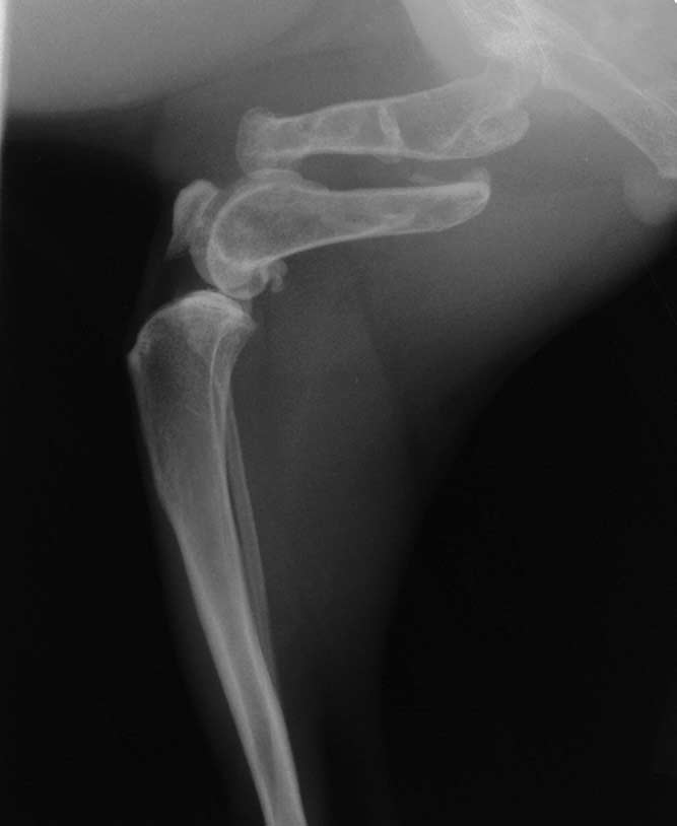

which OCD lesions are these in the dog

A = cd humerus

B = medial humeral condyle (elbow)

C = medial trochlear ridge (ankle)

D =lateral femoral condyle (knee)